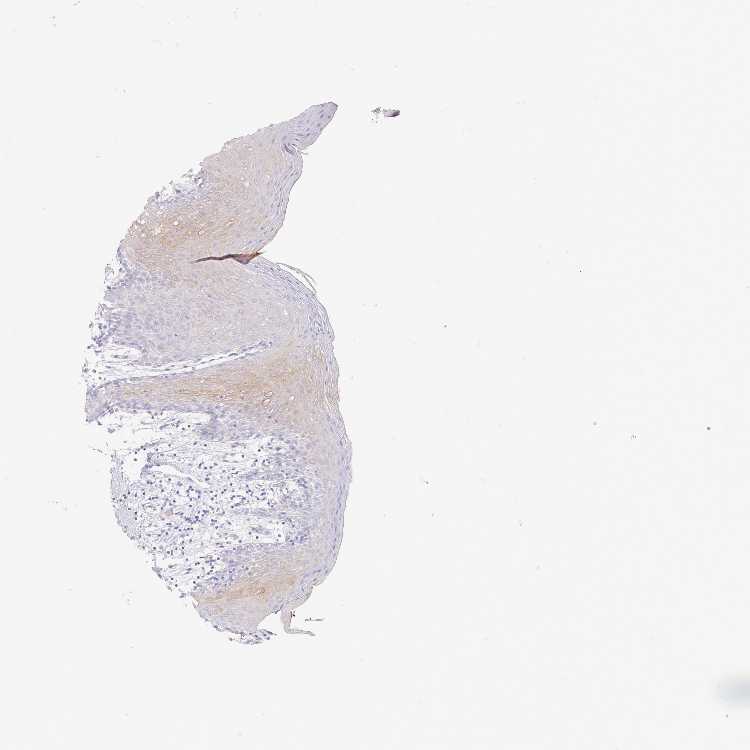

TISSUE PRIMARY DATA ORAL MUCOSA Show tissue menu

ORAL MUCOSA - Antibody stainingi

Antibody staining in the annotated cell types in the current human tissue is reported as not detected, low, medium, or high, based on conventional immunohistochemistry profiling in selected tissues. This score is based on the combination of the staining intensity and fraction of stained cells.

Each image is clickable and will lead to virtual microscopy that enables deeper exploration of all samples and also displays staining intensity scores, fraction scores and subcellular localization as well as patient and tissue information for each sample.

Antibody HPA044158Antibody HPA047913

Squamous epithelial cells Not detectedLow